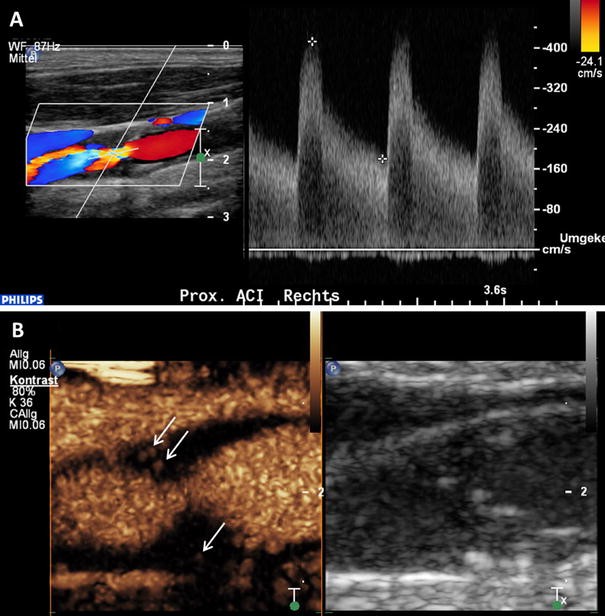

Intraplaque neovascularization within carotid stenosis on CEUS imaging. a 77-year-old patient with asymptomatic high-grade stenosis at the origin of the right internal carotid artery on Duplex ultrasound. b Extensive intraplaque neovascularization within the carotid stenosis at the near wall on CEUS imaging (arrows) and moderate neovascularization at the fare wall (arrow)